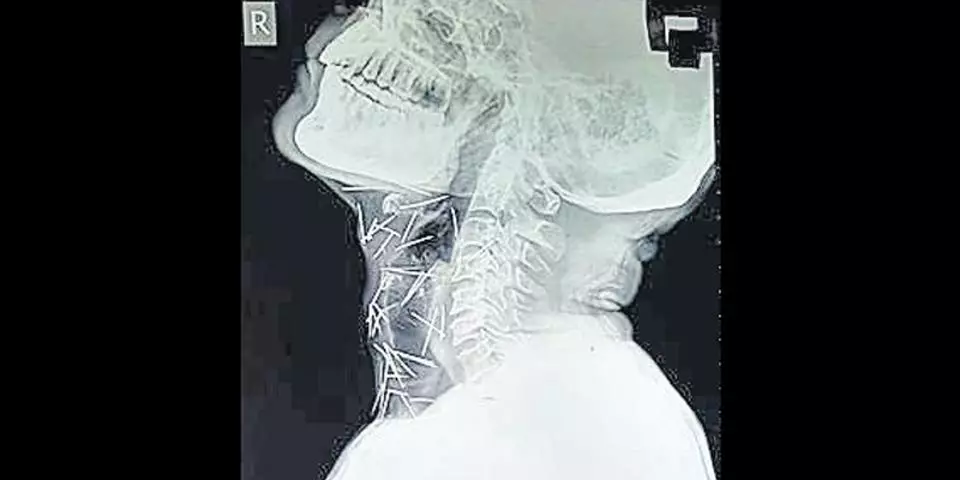

രാജസ്ഥാന് സ്വദേശിയും 56 കാരനുമായ ബദ്രിലാല് മീണ കാലുവേദനയും പ്രമേഹവും ശല്യപ്പെടുത്തിയപ്പോഴാണ് കഴിഞ്ഞ ഫെബ്രുവരിയില് ആശുപത്രിയില് പോകാന് തീരുമാനിച്ചത്. കോട്ട റെയില്വെ സ്റ്റേഷന് ആശുപത്രിയില് വെച്ച് സര്ജറിയും നടന്നു. അതോടുകൂടി തന്റെ ബുദ്ധിമുട്ടുകളെല്ലാം അവസാനിച്ചുവെന്നായിരുന്നു മീണ കരുതിയത്. സര്ജറിയുടെ വിജയമറിയാനായി ഏപ്രില് മാസമെടുത്ത എക്സറേയില് തെളിഞ്ഞത് ചില നടുക്കുന്ന സത്യങ്ങളാണ്.. വിവിധ ഭാഗങ്ങളിലായി 75 മൊട്ടുസൂചികളാണ് ബദ്രിലാല് മീണയുടെ ശരീരത്തിലുള്ളതായി എക്സറേയില് കണ്ടെത്തിയത്.

റെയില്വെ ജീവനക്കാരനാണ് ബദ്രിലാല് മീണ. ശരീരത്തില് തൊലിക്കുള്ളിലായാണ് ഈ പിന്നുകള് എല്ലാം എക്സറേയില് കണ്ടത് എന്നതാണ് ഡോക്ടര്മാരെ അമ്പരപ്പിച്ചിരിക്കുന്നത്. കഴുത്തിലും, കൈകളിലും കാലിലുമായാണ് പിന്നുകളിലധികവും കണ്ടെത്തിയിട്ടുള്ളത്. ഇത്രയധികം മൊട്ടുസൂചികള് എങ്ങനെ തന്റെ ശരീരത്തില് വന്നുവെന്ന് ബദ്രിലാല് മീണയ്ക്കും അറിയില്ല. ഇനി മറ്റാരെങ്കിലും ബദ്രിലാലിനെ ബോധം കെടുത്തിയോ മറ്റോ സൂചികളെ തൊലിപ്പുറത്തേക്ക് തുളച്ചു കയറ്റിയതാണെങ്കില് അത്തരം അടയാളവും തൊലിപ്പുറമെ ഇല്ലതാനും. ഈ സമസ്യക്ക് ഉത്തരം തേടുകയാണ് ബദ്രിലാലിനെ ചികിത്സിക്കുന്ന ഡോക്ടര്മാരും.

പ്രമേഹബാധിതനായതിനാല് സര്ജറി നടത്തി ഇത്രയധികം പിന്നുകളെ പുറത്തെടുക്കുക എന്നത് ബദ്രിലാലിന്റെ ജീവനെ അപകടത്തിലാക്കുമെന്ന് ഡോക്ടര് ഭയക്കുന്നു. 40 സൂചികളാണ് തൊണ്ടയില് കുടുങ്ങിക്കിടക്കുന്ന നിലയില് കണ്ടെത്തിയിരിക്കുന്നത്. വലതു കാലില് 25 എണ്ണവും രണ്ടെണ്ണം വീതം രണ്ട് കൈകളിലും തിരിച്ചറിഞ്ഞിട്ടുണ്ട്.